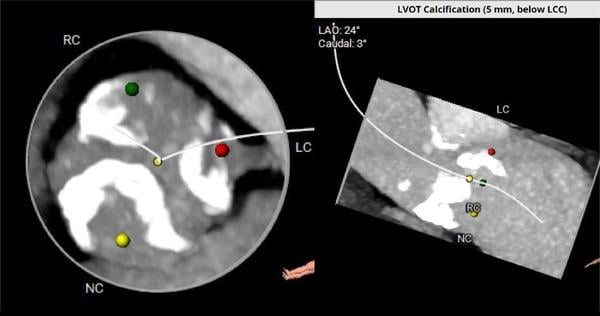

Die transthorakale Echokardiographie zeigte eine schwere Aortenklappenstenose mit einem mittleren Gradienten von 65 mmHg (Abbildung 1) und einer Aortenklappenöffnungsfläche von 0,6 cm². Die linksventrikuläre Auswurffraktion betrug 60 %. Erhaltene rechtsventrikuläre Funktion, geringgradige Mitral- und Trikuspidalregurgitation.

Abbildung 1: TTE